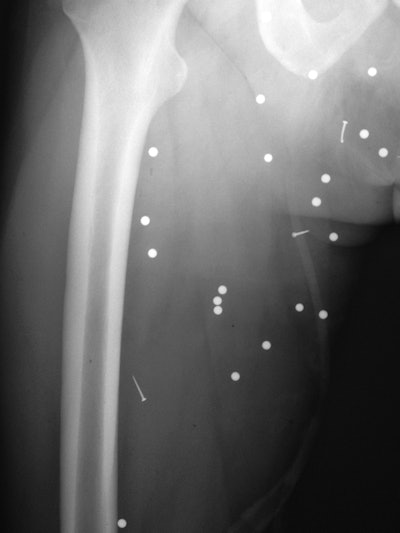

X-ray and CT showed a total of 189 shrapnel fragments in 32 (74%) of the 43 patients. Most of the objects (153, or 81%) were found in the soft tissues of the legs, thighs, and pelvis, while the remaining 19% were located above the pelvis or in the foot. The number of objects per patient ranged from one to 41 fragments.

Shrapnel from a secondary blast wave caused a fracture of the distal tibia and fibula in a patient's right leg. All images courtesy of AJR.Clinicians also found a large variety of debris embedded in patents. There were 125 ball bearings, 44 metal fragments, 10 nails, one screw, and nine pieces of gravel or other foreign objects. In addition, 11 patients had fractures in areas including the foot, leg, thigh, hand, orbit, nose, and lumbar spine. Injuries to five of the patients were so severe that they required lower-limb amputations.

The secondary blast wave propelled multiple ball bearings and nails into the soft tissue of a patient's right thigh.Tertiary blast injuries result from falling or being thrown back by an explosion, according to the authors. In this category, right-sided lumbar transverse process and nasal bone fractures were found in two patients, along with a tibial shaft fracture in a third patient without any associated shrapnel or skin breech.